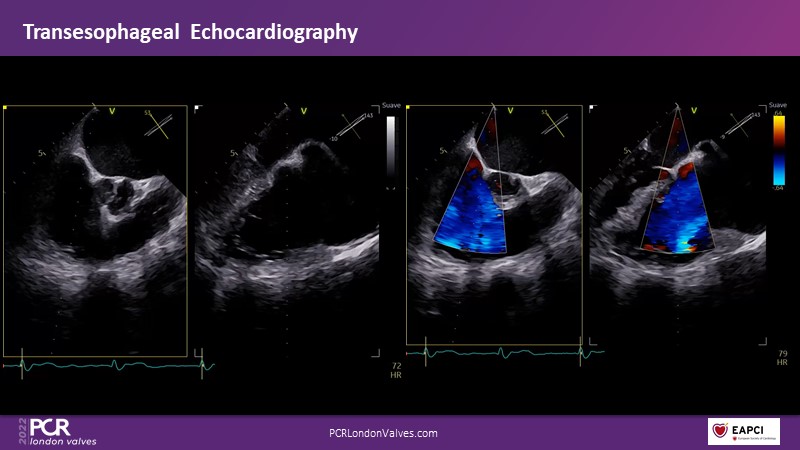

Watch this session if you want to learn tips and tricks that influence procedural strategy through a real-life case as well as anatomical factors that contribute to tricuspid valve complexity and choice of treatment, followed by the latest clinical data.

- To learn more about the anatomical factors that contribute to tricuspid valve complexity and choice of treatment

- To share tips and tricks that influence procedural strategy through a real-life case